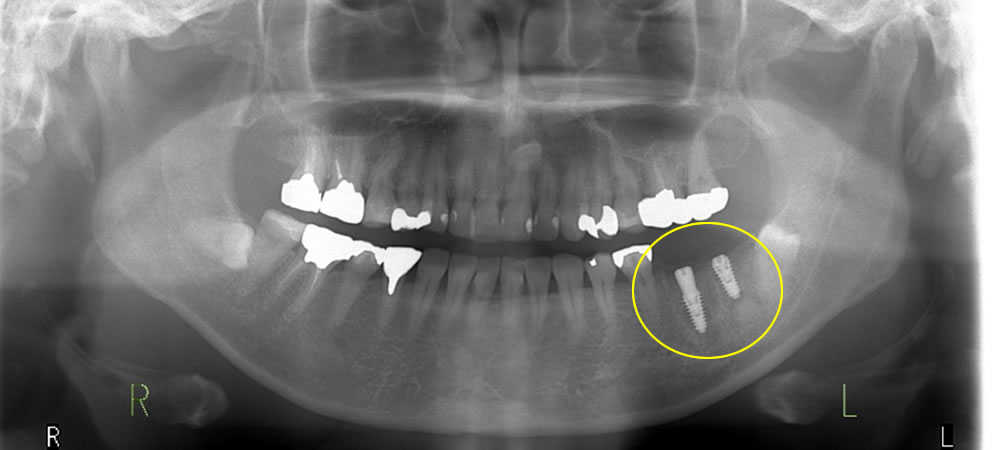

手術は静脈内鎮静法、抜歯、インプラント埋入、人工骨の使用、縫合で来院からご帰宅まで約3時間で終了しました。

術後はインプラント部分のCT撮影とパノラマ撮影で確認します。約5ヵ月間の結合期間(骨とインプラント体の結合期間)を設け、歯肉の処置と型どりを行ってかぶせ物を作製します。